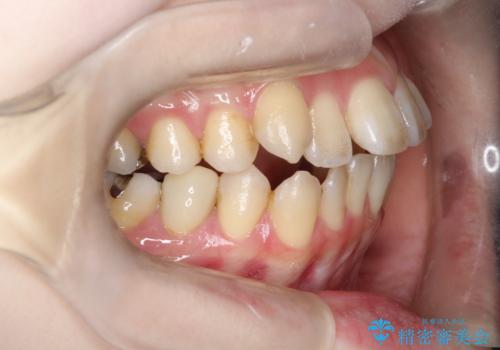

開咬や歯列のデコボコが改善され、見た目だけでなく咬み合わせの機能面も大きく向上し、大変ご満足いただけました。

また、治療期間も比較的短期間で終了することができました。